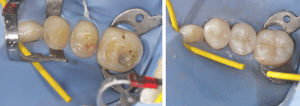

Mme AB vient en consultation pour deux raisons. La première est une douleur intense à chaque fois qu’elle boit ou mange froid. La deuxième est l’apparence de son sourire. Elle trouve que ses dents ont « raccourci » et qu’elles « s’effritent ». C’est devenu un complexe handicapant. À L’examen clinique on observe (Fig.1a, b, c, d, e) une usure vestibulaire de toutes les dents : plus prononcée au maxillaire et assez légère sur les incisives mandibulaires, une classe III canine et molaire droite, une classe I canine et molaire gauche avec une légère déviation des milieux et une usure importante des faces palatines du bloc IC maxillaire ainsi que des faces occlusales de 16 et 26. On constate aussi que les faces occlusales des autres dents sont moins touchées en apparence. On observe que les amalgames de 36 et 48 sont en relief par rapport à la dent support. Il est raisonnable de supposer qu’à l’origine ils devaient obturer une cavité et donc être à l’intérieur de la dent. Ceci témoigne donc aussi d’une forte usure sur 36 et 46. On observe enfin que les courbes de Spee sont complètement plates.

Fig.1a, b, c, d, e : Examen clinique.

Fig.1b.

Fig.1c.

Fig.1d.

Fig.1e.